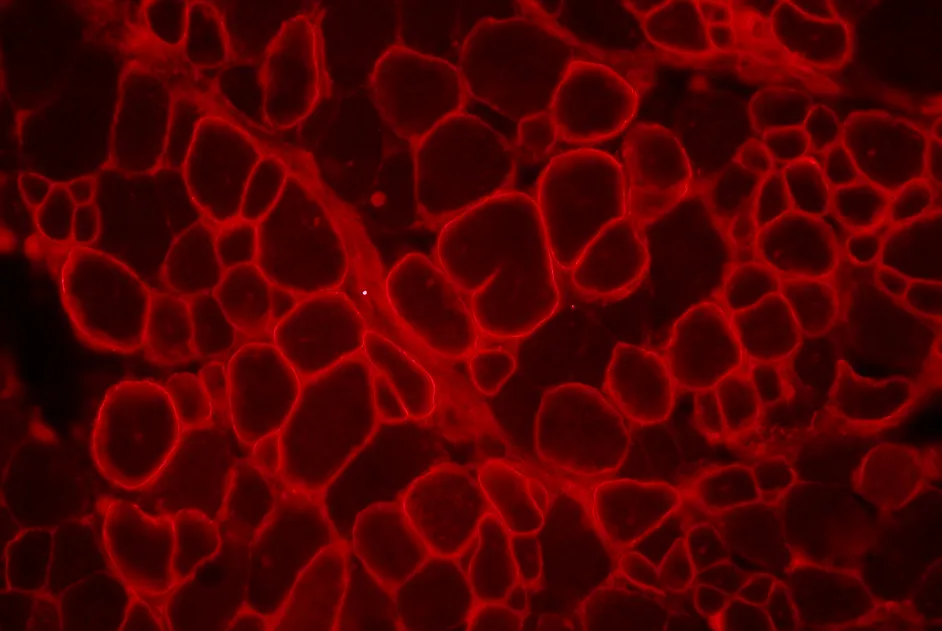

La modification de l’enveloppe d’un vecteur viral pour apportant la microdystrophine chez le jeune chien est efficace et attenue la réponse immunitaire.